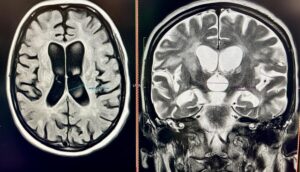

40-річна Соломія не могла самостійно дихати, їсти, розмовляти та ходити. Саме у такому стані вона потрапила у приймальне відділення Університетської лікарні. З 2018 року Соломія страждає на розсіяний склероз, але жодного разу не лікувала це захворювання. Коли вона вже була без свідомості, мама викликала “швидку”

Замість Соломії дихав апарат ШВЛ, замість повноцінної їжі вона отримувала спеціальне харчування через назогастральний зонд. Крім неврологічних проблем, у пацієнтки діагностували важке токсичне ураження печінки, тромбоемболію легеневих артерій, тромбофлебіт (запалення стінок вен і формування тромбу у судині) у нозі і запалення вуха.

Жінка пройшла курс спеціалізованого лікування, в тому числі пульс-терапію.

«Частина змін для Соломії незворотні, але вона ми отримали добрий результат. Після реабілітації пацієнтка зможе ходити і обслуговувати себе сама, супутні патології ми також пролікували, тож вона почувається значно краще. Далі вона отримуватиме хворобомодифікуючу терапію, яка зможе зупинити прогресування хвороби”, – пояснила Мар’яна Бойчук, завідуюча неврологічного відділення.